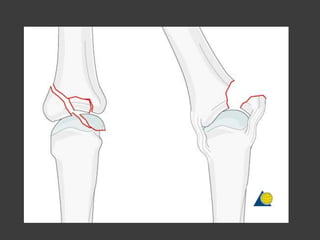

Fx de la cabeza de los

metacarpianos

Fijación de fragmento grandes -

anterogrado

Fijación de fragmentos

pequeños - retrogrado